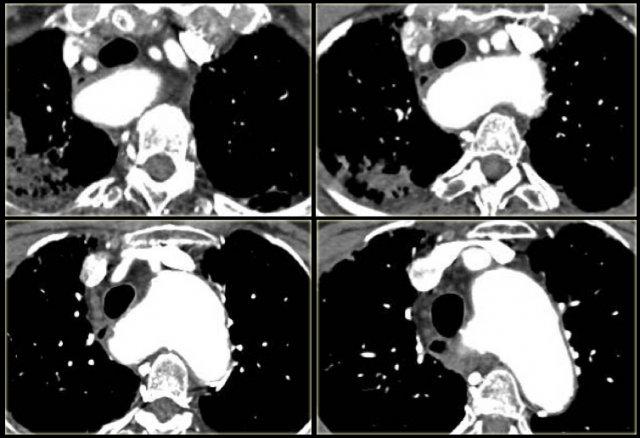

Aortic Coarctation

- Narrowing at level of distal arch / descending aorta.

- Chest film: ‘figure 3’ sign, inferior rib notching.

- Intervention when gradient > 20 mm Hg.

- Associated with bicuspid aortic valve (75%), cerebral aneurysms (5-10%) and Turner syndrome (20% have coarctation)

On the left a 2 month old boy with heart failure.

First study the image, then continue

The findings are:

- Large thymus which is normal for a 2 month old.

- Striking discrepancy between diameter of ascending and descending aorta.

The diagnosis is coarctation, which is nicely demonstrated on the posterior view of the reconstruction.

There are two types of coarctation.

The type we usually see is the post-ductal type, which is distal to the left subclavian artery.

The uncommon pre-ductal type is seen in neonates.

They present with severe heart failure, mostly within the first week of life, usually on the first day.

The occlusion is in front of the left subclavian.

First study the axial image followed by the sagittal reconstruction, then continue.

- Big internal mammarian arteries on the axial image due to a high grade stenosis as a result of a coarctation. Probably could not make the diagnosis based on the axial images alone.

- Post-ductal coartation only seen on sagittal reconstruction.

- Intercostal collaterals.

The intercostal collaterals typically occur between the 3rd and the 8th rib.

On the left two neonates with the pre-ductal type of coarctation.

The stenosis is in front of the left subclavia and there is arch hypoplasia.

Collaterals do not occur, probably because they don’t have time to develop.